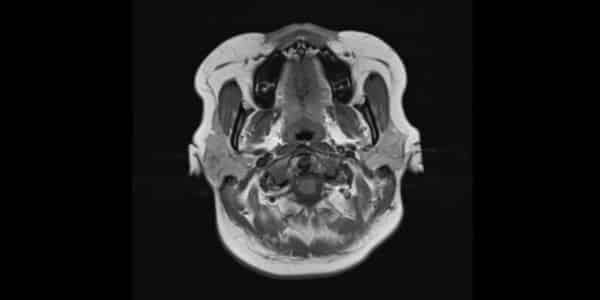

Resonancia de cerebro/cabeza

La resonancia magnética (RM) de cerebro es un examen que genera imágenes precisas del encéfalo, los vasos sanguíneos, los nervios craneales y otras estructuras internas del cráneo.

Este estudio es clave para identificar y analizar diversas afecciones del sistema nervioso central, como tumores, accidentes cerebrovasculares, malformaciones congénitas, esclerosis múltiple, infecciones, aneurismas o las causas de dolores de cabeza crónicos, facilitando un diagnóstico detallado y un seguimiento efectivo del tratamiento.

Precio desde: 170€